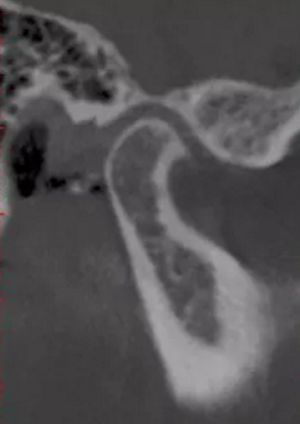

正常情況下,我們的上前牙是蓋在下前牙唇側(cè)3mm內(nèi)的,上下切牙牙軸交角為125°左右,

但前牙閉鎖合是上前牙下垂伸長(zhǎng),內(nèi)扣完全鎖住了下切牙,正面觀時(shí)我們??床坏较虑醒溃虑醒绖t常擁擠伸長(zhǎng)咬到了上腭內(nèi)的牙齦上,上下前牙發(fā)生的交角幾近180°。

正常前牙交角

前牙閉鎖合交角

前牙正常覆合

前牙閉鎖合-深覆合

前牙正常覆蓋

前牙閉鎖合覆蓋